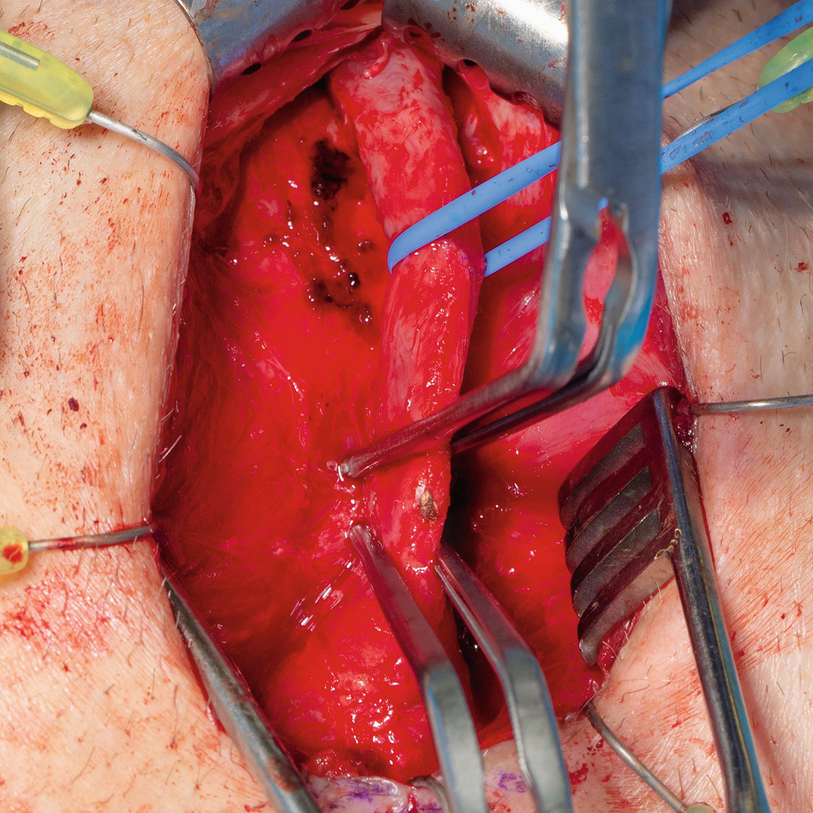

Following circumferential exposure distally, a vessel loop facilitates atraumatic retraction during additional proximal bulbar mobilization